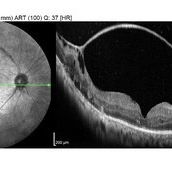

Macular Hole RD

Apr 5 2018 by Mohamed Tawfik, MD

OCT image of a case of macular hole RD show improved of anatomical view with improving of vision.

Photographer: Mohamed A,Tawfik MD , FRCSed

Condition/keywords: macular hole